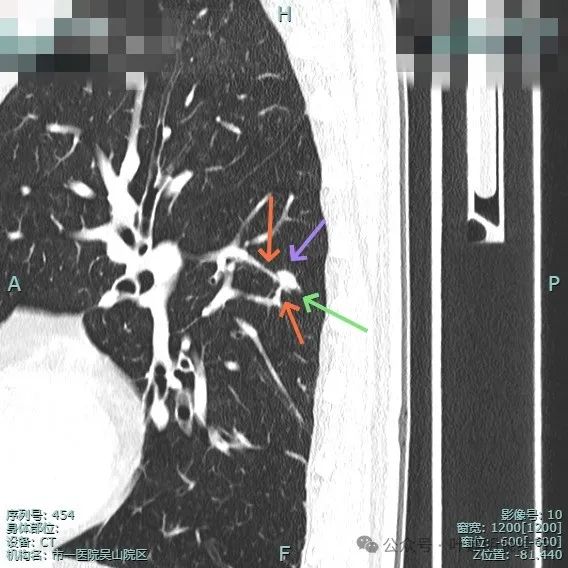

细小毛刺可见,少许磨玻璃成分,整体轮廓较清。

邻近血管与之近但两者间有间隙,说明非普通伴水肿的炎性病灶;病灶膨胀感显得较明显,有鼓鼓的感觉。

进入的血管壁显得毛糙,有异常增粗,结节与邻近血管之间有间隙征,整体有膨胀感。

病灶表面细锯齿状,整体膨胀性明显,血管进入并异常增粗,整体轮廓清,周围肺野清晰。

病灶表面不平,形态略不规则,血管进入,边缘细锯齿状。